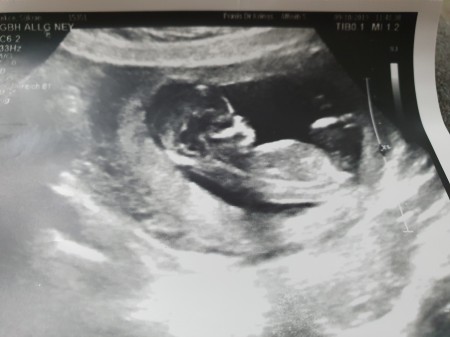

Sizce cinsiyetini ne doktor bize bisey demiyor kesin cevap olarak  bana kalırsa kıza benziyo dedi

Gebelik haftası 22-2

Bence de kiza  benziyo

Ben erkeğe benzettim canım rabbim hayırlı olanı versin inşallah hiç tahminde de bulunmadı mı

Kesin bisey demiyorum en son doktora gittiğimde bacaklarıyla saklamıştı kendini göstermedi ama doktor kalırsa kız dedi